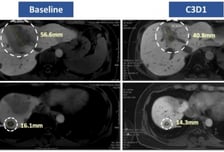

보로노이가 지난 9일부터 오는 12일까지(현지시간) 미국 샌안토니오에서 열리는 유방암 심포지엄(SABCS 2025)에서 인간 상피세포 성장인자 수용체2(HER2) 고형암 표적 치료제 'VRN10'의 임상 1상 최신 결과를 발표했다고 12일 밝혔다. VRN10의 임상 1상은 한국과 호주에서 HER2 양성 또는 HER2 돌연변이 고형암 환자를 대상으로 진행 중이며, 이번 발표는 지난 10월 열린 '미국암학회(AACR)-미국국립암연구소(NCI)-유럽암연구치료기구(EORTC) 국제 컨퍼런스'에서 공개된 80mg 및 160mg 용량 데이터에 이어 240mg 투약군까지의 데이터를 포함했다. 이번 발표에 따르면 VRN10은 초기 용량임에도 불구하고 괄목할 만한 항종양 효과를 보였다. 80~160mg까지의 초기 투약군 환자 중 3명에서 종양 감소가 확인됐고, 그 중 1명은 종양 크기가 30% 이상 줄어드는 부분관해(PR)를 달성했다. 특히 HER2 타깃 항체-약물접합체(ADC) '엔허투'를 포함한 기존 치료제에 불응하고 종양이 진행된 HER2 변이 유방암 환자에서도 30% 수준의 종양 감소를 보여 폭넓은 치료 가능성을 입증했다.